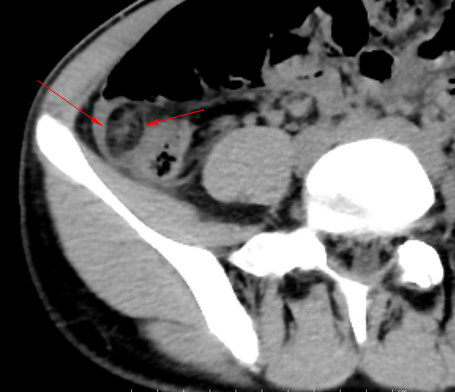

• 超音波検査

• CT検査